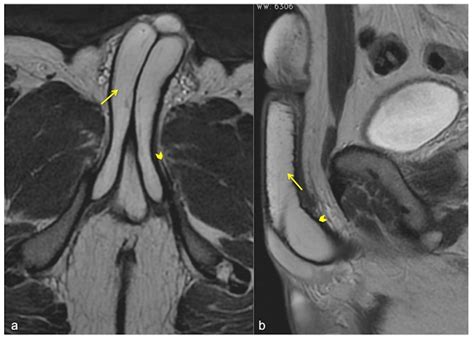

A penile fracture is a rupture of the tunica albuginea due to blunt trauma while the penis is erect. The classic radiological finding is a defect or “discontinuity” in the low-signal-intensity tunica albuginea. MRI is particularly useful here to demonstrate the exact site of the tear and the extent of the surrounding hematoma.